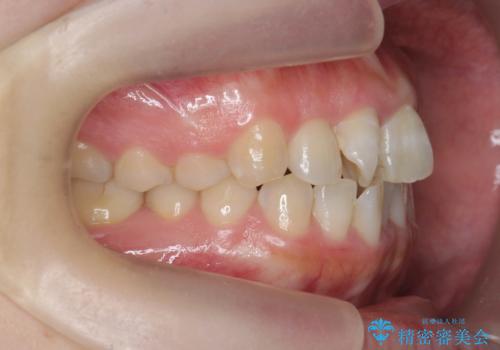

- 前歯のねじれを改善したい、と矯正治療を希望され来院されました。

上下の歯のがたつきを改善するマウスピース矯正治療と、下顎に見られる大きな骨隆起を外科的に除去する治療計画を進めていきます。

歯並びが改善したとともに、骨隆起を除去したことで舌をしまうスペースも増え安定した口腔内環境を確立することができました。